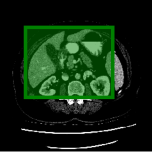

Consider a three-dimensional object within a volume. It is straightforward to produce a 3D bounding box of the object by finding its extreme points in the three coordinate axes. While this 3D bounding box will be tight in the 3D sense, its rectangular cross-sections will not, in general, remain tight with respect to the planar cross-sections of the volume. Fig. 1 illustrates such a case for the task of liver segmentation in a CT volume. In the Experiments section we show that the success of existing 2D weakly-supervised segmentation methods relies on the bounding boxes being tight and therefore the tightness of the individual 2D bounding boxes should be corrected before training and applying a segmentation CNN.

(a)

(b)

(c)

(d)